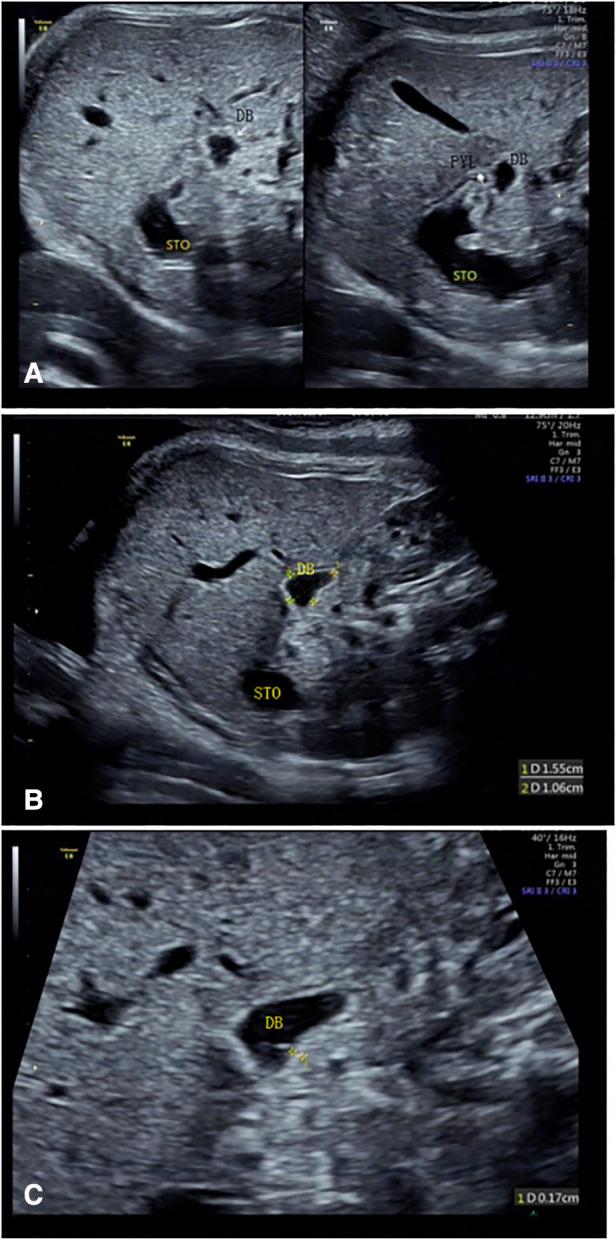

To use the fetal pylorus as a reference point to conveniently display the normal fetal duodenum by ultrasound.

This study was designed in cross-section. A total of 450 healthy singleton pregnant women at 19-39 weeks of gestation who underwent prenatal screening at our hospital from January 2019 to February 2020 were selected. They were divided into three groups according to gestational weeks: the 19-23 gestational weeks group, 29-32 gestational weeks group, and 34-39 gestational weeks group. The duodenal bulb was identified. Its movement and course were continuously and dynamically observed. The descending part of the duodenum was identified, and the duodenal course was traced.

The fluid-filled in the fetal duodenum was discontinuous. The overall detection rates of the duodenum in the 19-23 gestational weeks group, 29-32 gestational weeks group, and the 34-39 gestational weeks group were 82.2%, 26.2%, and 13.8%, respectively. The detection rates of the bulbar, descending, horizontal, and ascending parts of the duodenum were 94.4%, 58.2%, 58.0%, and 52.0%, respectively. The anatomical structures of the duodenum as a whole and the pancreas were most easily recognized in the 19-23 gestational weeks group; while in the 34-39 gestational weeks group, the bulbar part had a maximum detection rate of 98.8%, and it had the longest filling time and the shortest examination time.

The pylorus is an ideal starting point for tracing the fetal duodenum. The overall detection rate of the fetal duodenum decreases with gestational age. The duodenal bulb is the most easily detected site.